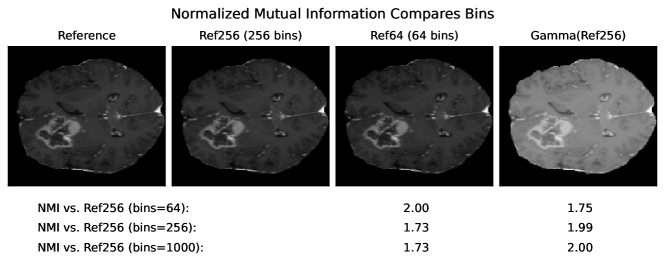

2.8 Statistical Dependency Metrics

Mutual information (MI) and normalized mutual information (NMI) estimate the amount of information of an image , that can be predicted from image .

MI is widely used for multi-modal image registration, and it was shown, that it correlates to the degree of spatial transforms [50]. It has been used sporadically as a metric for image synthesis [33, 23].

While MI ranges between 0 and infinity, NMI has a range of , which is preferable for comparing absolute metric scores and interpretability.

5 Adverse Examples

In the following, special characteristics of the analyzed metrics, which can be derived from their definition or the experimental results above, are show-cased. We present adverse examples (see Fig. 2-6), where similarity metrics do not perform as intended or expected.